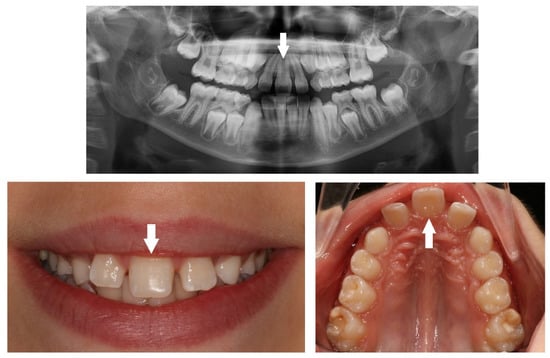

| Peg-shaped | Small conical tooth with a narrowing in diameter from the cervix to the in-cisal edge. |

| Impaction | Failure of tooth eruption into the oral cavity. |